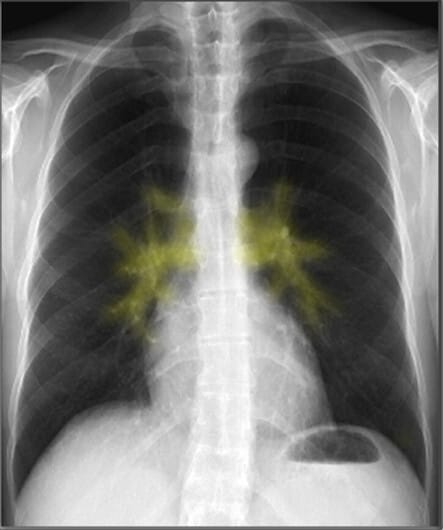

| 폐문 (Hila) |

| ✅ 폐동맥, 기관지, 림프절 등이 위치하는 부위로, 좌측이 우측보다 약간 높게 보이는 것이 정상입니다. 폐문이 커지거나 밀려 있다면 종양, 폐부종, 림프절 비대를 고려해야 합니다. |

종격동(mediastinum)은 심장과 주요 혈관, 기관(trachea) 등이 위치하는 공간으로, 이들의 크기와 모양을 분석하는 것이 중요합니다.

| 대동맥궁 (Aortic Arch) |

| ✅ 좌측 폐문(hilus) 위에서 둥글게 보이며, 확장되거나 비대해지면 대동맥류 또는 고혈압성 변화 가능성을 고려해야 합니다. |